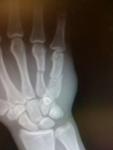

Сломанная рука Юрая Фрайбера, после боя.